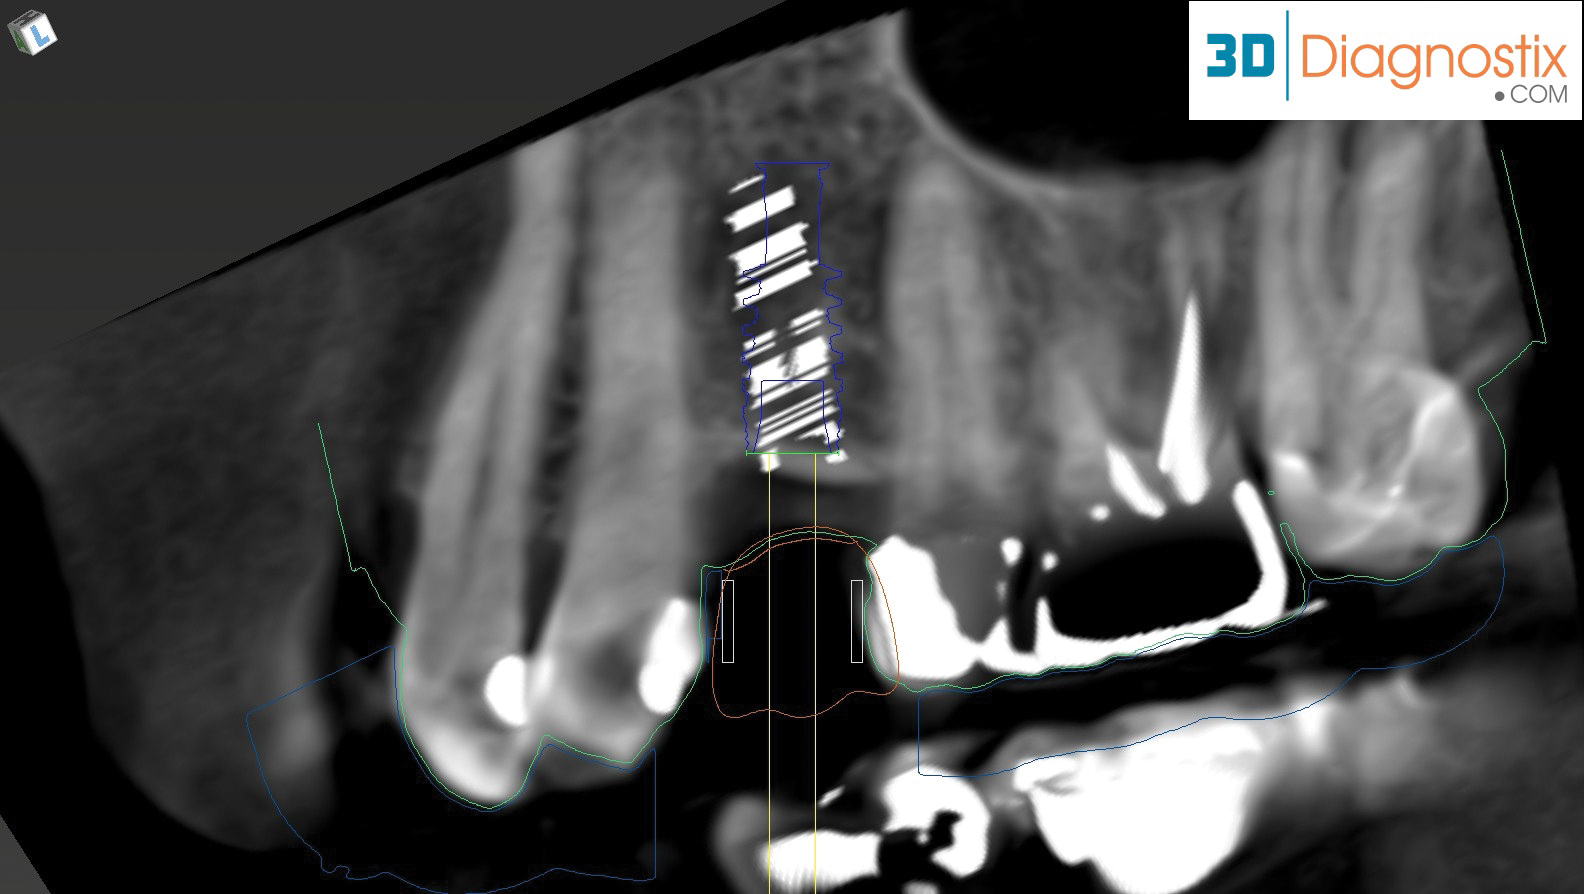

Fig 9. By merging CBCT files with IOS files and using implant planning software, dental professionals can plan all components of the implant/restoration procedure in advance for a restoratively driven approach: CBCT, IOS, and CAD merged and overlayed as one (Fig 9); implant placement and implant guide CAD (Fig 10).

Figure 9